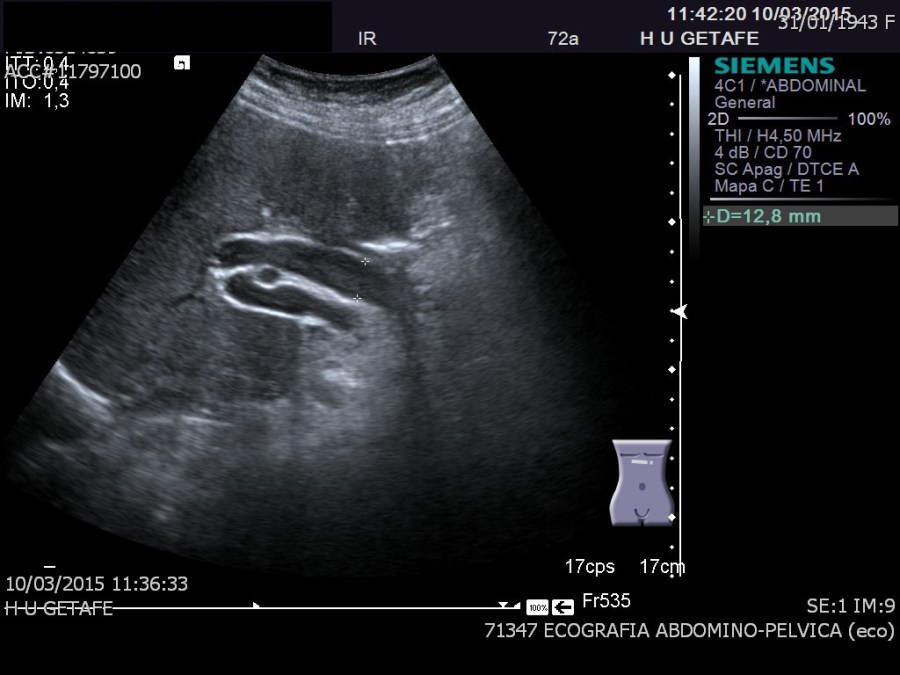

Cuando hablamos del Hilio Hepático, hablamos de una porción anatómica muy importante desde le punto de vista de la exploración ecográfica dentro del protocolo de Abdomen. La imagen que te pongo a continuación es difícil de conseguir, técnica y anatómicamente, pero a veces, nos encontramos este corte parasagital que nos da una información fabulosa y una correlación anatómica perfecta del la vía biliar extrahepática, arteria hepática y vena porta.

Hoy nos vamos a parar exclusivamente en la consecución de esta imagen, que depende de cada paciente, será un corte parasagital y la conseguiremos en decúbito lateral izquierdo. No es vinculante la imagen del pictograma que aparece en la imagen, cada paciente necesitará una orientación, este concepto es vital.

Este corte es un corte parasagital, donde el transductor está paralelo tanto al eje largo de la porta como al eje largo de la vía biliar extrahepática, que como vimos muchos capítulos atrás son paralelas, siendo la vía biliar extrahepática anterior a la porta, siendo la porta, referencia para buscar la vía biliar.

Entre ambas discurre, perpendicularmente, la arteria hepática. Por eso en este corte nos la vamos a encontrar como una circunferencia, entre dos estructuras tubulares.Es una imagen de una belleza brutal, difícil de conseguir, ya digo, pero debemos buscarla siempre.

La relación anatómica de la ecoestructura es esta. Observa la medida, marca una elevación anormal de los estándares de medición para la vía biliar extrahepática o colédoco, si a estos pacientes con esta medida del colédoco no les encontramos causas justificadas para esta dilatación, acabarán haciéndose una Colangio Resonancia Magnética para demostrar la causa de dicha dilatación, patológica, según la literatura, por encima de 1 cm, considerando que cada 10 años que cumplimos, nuestra vía biliar extrahepática puede aumentar 1 mm. Es decir, para un/a paciente de 40 años, la normalidad de esta medida será en torno a 0,4 cms, para uno de 70, 0,7 cms, en este caso, de 72 años, mide 12,8 mms, claramente anormal.

Las causas de esta dilatación son variadas, desde colédocolitiasis hasta tumoraciones de la cabeza pancreática, por eso es vital el estudio de dicha región con minuciosa rigurosidad.

Algunxs pacientes con patología son asintomáticxs, además debemos saber que en pacientes colecistectomizadxs podemos encontrar dilataciones de calibre superior al estándar y ser normales.